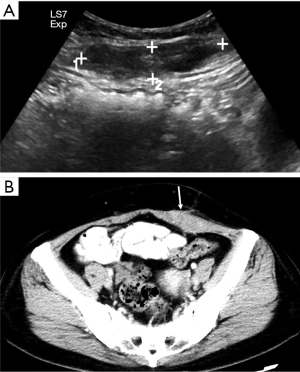

Endometriosis

The anterior abdominal wall is the most common site of extrapelvic endometriosis, which usually develops in a cesarean section scar, with a wide range of reported incidence rates of 0.03–3.5% (60). The most plausible cause of scar endometriosis is implantation of endometrial stem cells at the surgical site at the time of uterine surgery. Anterior wall endometriosis in patients with no prior surgeries is rare (61). Abdominal wall endometriomas are often the only manifestation of endometriosis with no associated pelvic endometriosis. The typical presentation is a female patient with cyclical pain from a mass in scar tissue (62).

The appearance of abdominal wall endometriosis on CT and MRI depends on the phase of the patient’s menstrual cycle, the chronicity of the process, the number of stromal and glandular elements, and the amounts of bleeding and associated inflammation (63). On CT, anterior abdominal wall endometriosis typically appears as a solid soft tissue mass that is hyperattenuated compared with muscle, although the attenuation can vary and be nonspecific. On MRI, it typically presents as a solid mass that is mildly hyperintense on both T1WI and T2WI as a result of subacute hemorrhage within the endometriotic crypts, although this finding may also vary (Figure 13). Mild to moderate contrast enhancement is present (60).